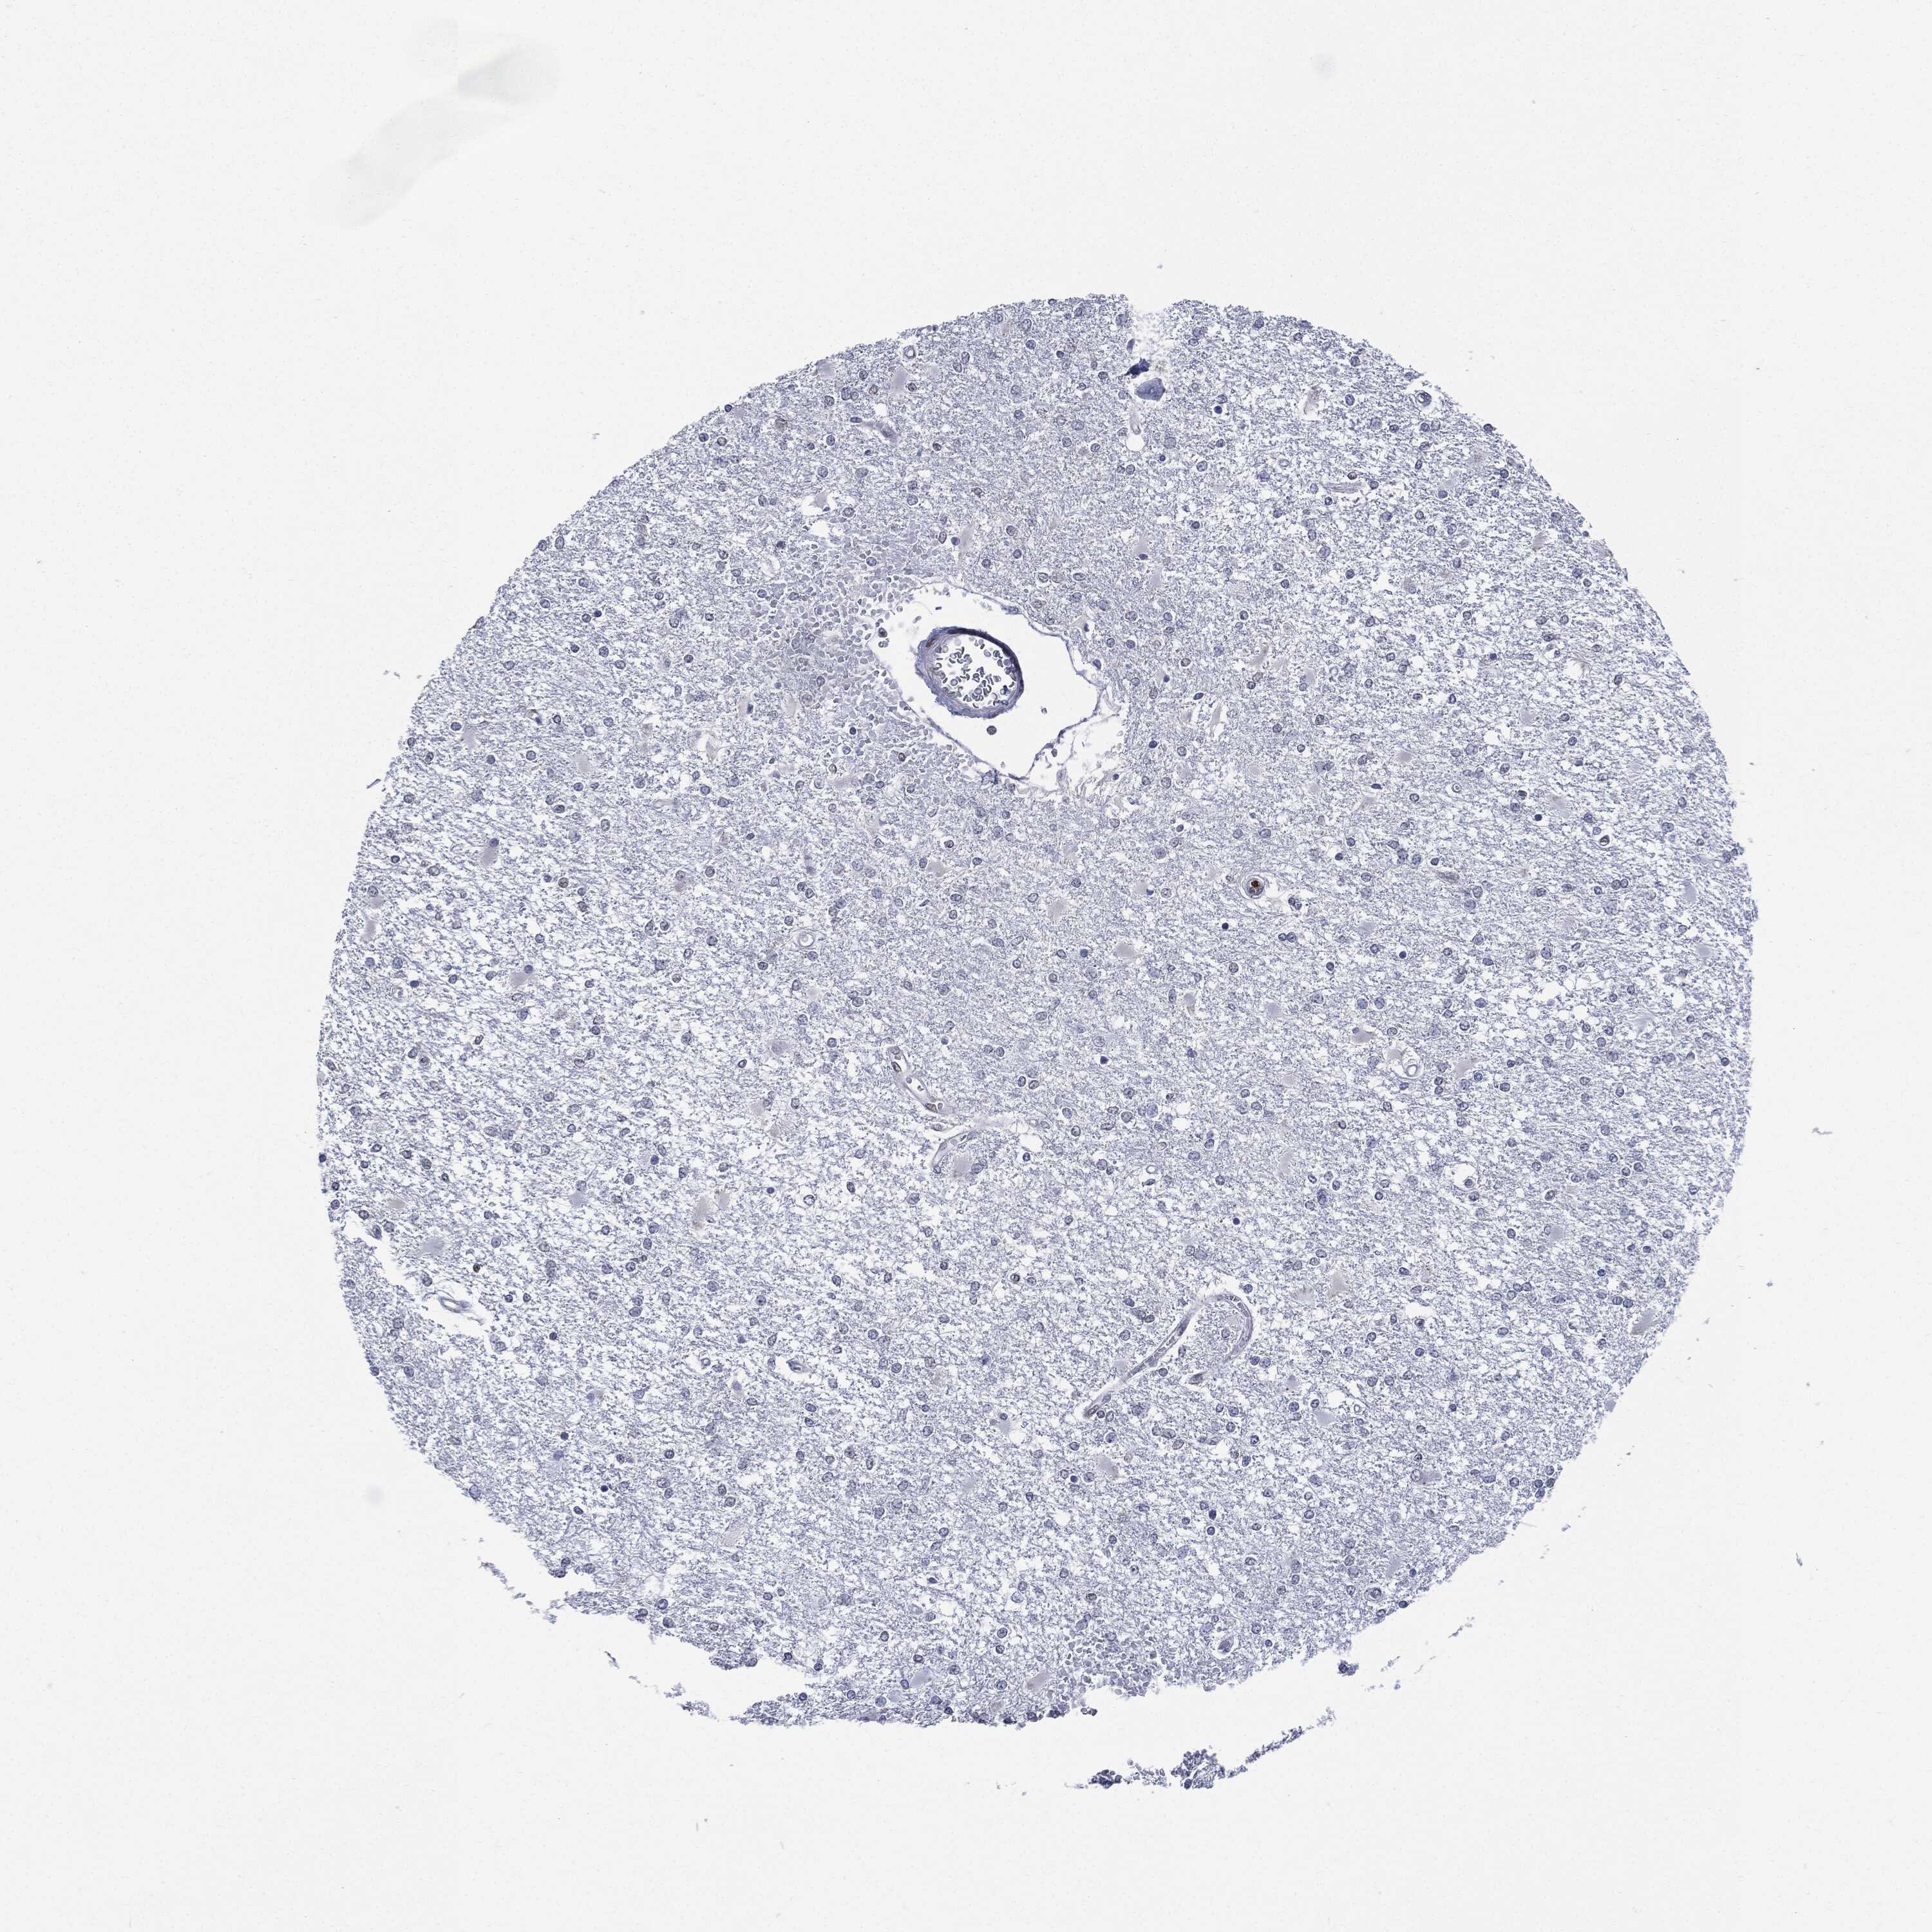

GLIOMA - Protein expressioni

A mouse-over function shows sample information and annotation data. Click on an image to view it in a full screen mode. Samples can be filtered based on level of antibody staining by selecting one or several of the following categories: high, medium, low and not detected. The assay and annotation is described here.

Note that samples used for immunohistochemistry by the Human Protein Atlas do not correspond to samples in the TCGA dataset.

Antibody stainingi

Antibody staining in the annotated cell types in the current human tissue is reported as not detected, low, medium, or high, based on conventional immunohistochemistry profiling in selected tissues. This score is based on the combination of the staining intensity and fraction of stained cells.

Each image is clickable and will lead to virtual microscopy that enables deeper exploration of all samples and also displays staining intensity scores, fraction scores and subcellular localization as well as patient and tissue information for each sample.

Glioma, malignant, High grade

Glioma, malignant, Low grade

Glioblastoma, NOS